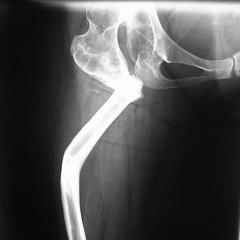

Bolnjia 30 let, stradaet ot vrozdennogo vyviha bedra, hodila i zila sebe spokoino, poka ne nashelsya hirurg, kotory pytalsa uluchit' eezhizn' i pohodku i v rezultate poluchilas', kak Vi vudete.

KAK MOZHNO EI POMOCH"????????????????Ei bilo predlozeno THR! No , ---- est' mogo no, est' bolee realnoe reshenjie??? Spasibo Zaranee vsem uchastnikamYours Dr. Castro